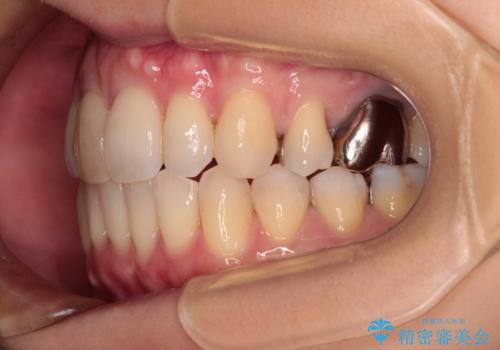

- 口を閉じたときに飛び出してしまう上顎前歯を気にして来院された患者様です。

上下の咬み合わせは上顎歯列全体が歯1本分前にずれている状態であり、さらに上顎歯列はV字型に尖っていたため、上下前歯は全く接触していない状態でした。